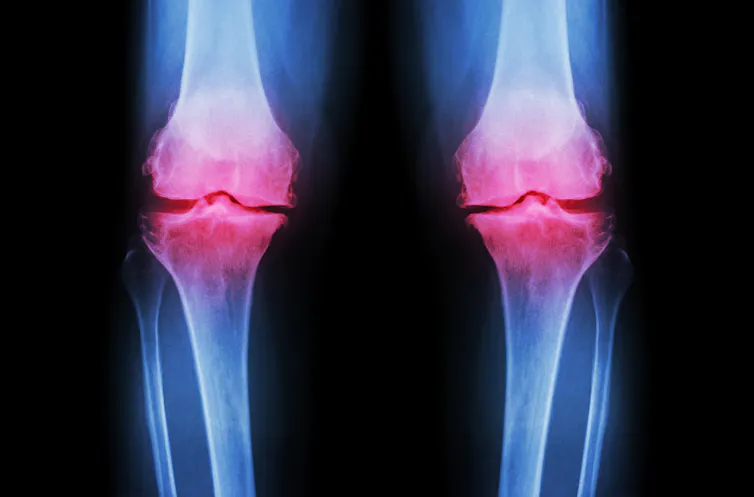

An X-ray of both knees reveals a narrow space between joints caused by loss of cartilage.

Puwadol Jaturawutthichai/Shutterstock.com